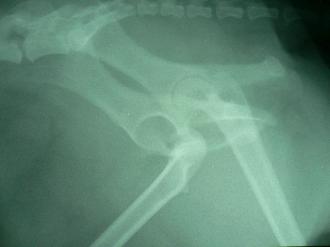

異常を察した飼い主さんは、急ぎ病院へ直行しました。身体検査では、かなりの痛みを感じます。股関節の解剖学的異常を感じ、早速レントゲン撮影に進みました。右の写真の通り患肢は後方へ脱臼していたのでした。